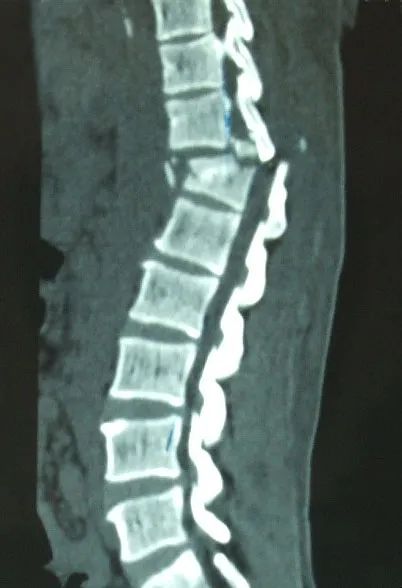

駝背、變矮、腰腿痛

X線攝片只有在骨量減少達(dá)到30%以上后,才能通過X射線檢查出來,對于早期骨質(zhì)疏松癥狀很難發(fā)現(xiàn)。而該儀器對于診斷骨質(zhì)疏松、評估骨折風(fēng)險及骨質(zhì)疏松治療效果能得到精確評價。